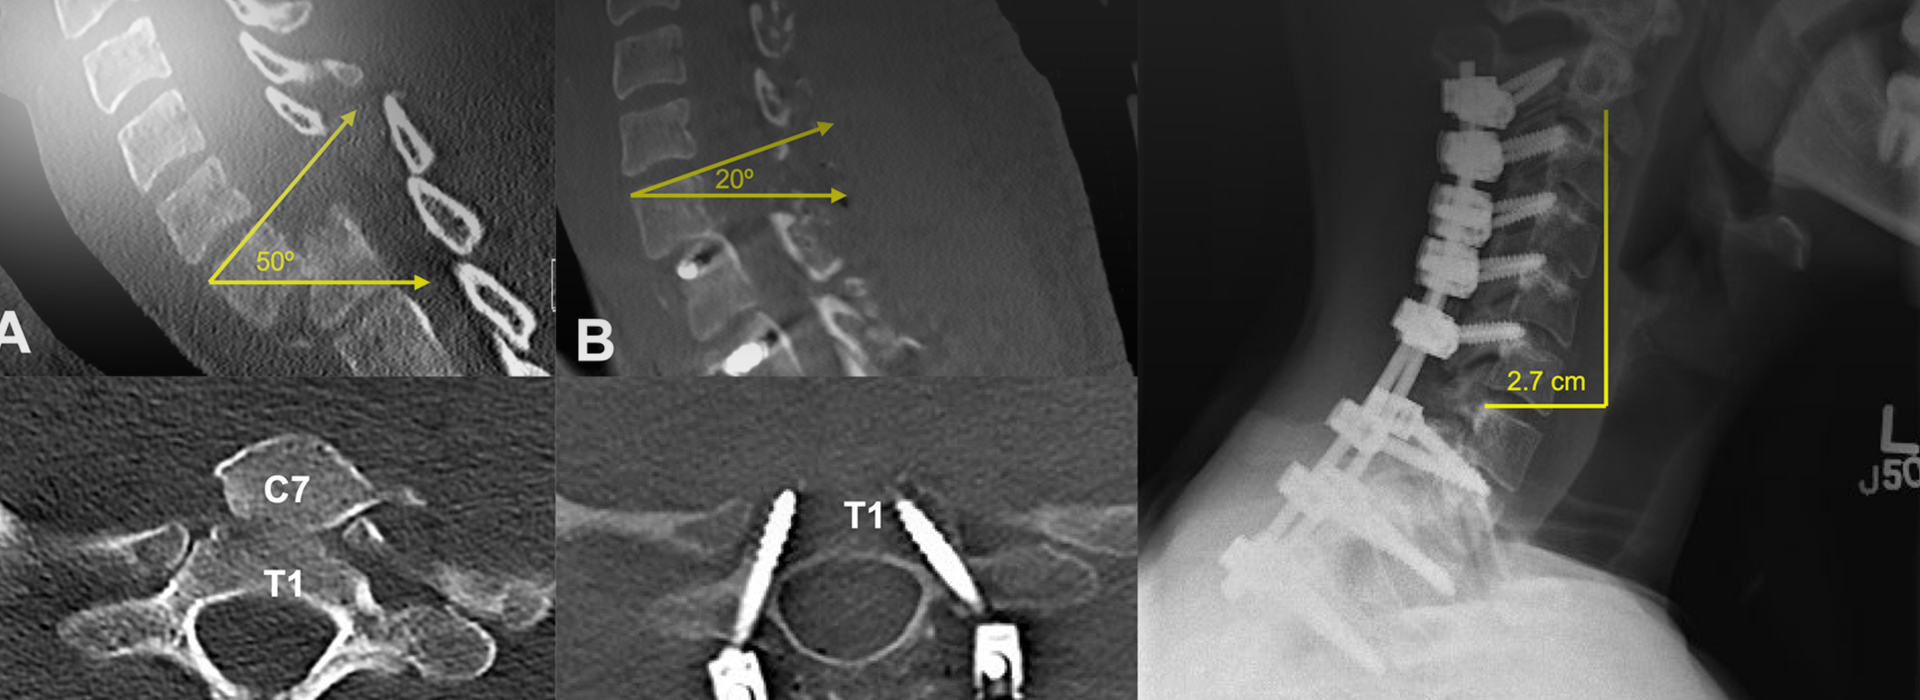

- Surgical Interventions: For unstable slips, procedures like spinal fusion, performed by a skilled spine specialist doctor, realign and secure vertebrae, reducing risks.